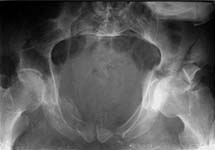

Today his left humerus and both ulnae were nailed. All closed. I attach two more images of the pelvis (inlet and Judet - i failed to find plain AP view). As his doctor told, he also has bilateral sciatic palsy, and severe calcaneus fracture. Anesthesologists tell that he will be ready for acetabular surgery not earlier than in a month. :-( He is in an external fixator with femoral extension. If femoral fragments looks aligned, and anyway fixator stays in place until the acetabular surgery, and maybe later, the femoral nailing today is probably for nothing.

Your fixator pins may burn some bridges for you in terms of approach for the acetabulum. This is clearly a complex acetabular fracture, and an extensile approach or more than one non-extensile approach may be required. I can't tell at this point, because you haven't supplied us with an adequate radiographic evaluation (2 Judet views, an AP pelvis and a CT scan). The inlet is helpful, but at first look, this appears to be an acetabular fracture, not a pelvic ring injury.

He has two column fracture with wing extension, but also a posterior ring injury.